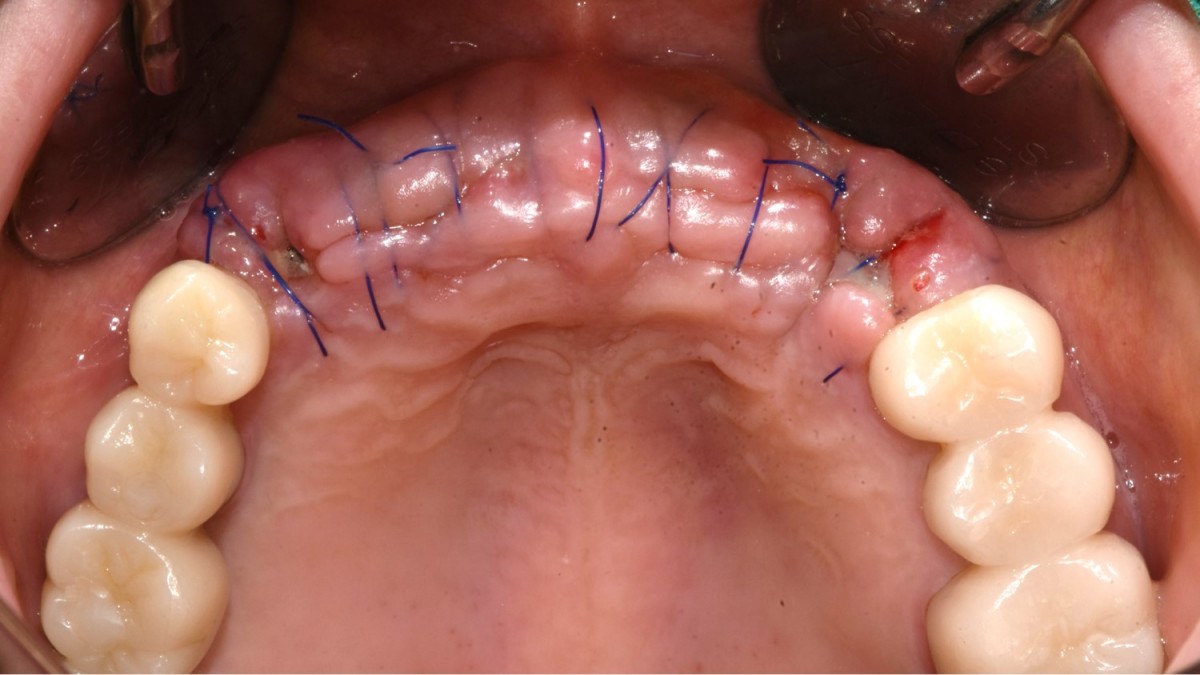

▲Implant placement GBR

▲GBR(Xenograft).